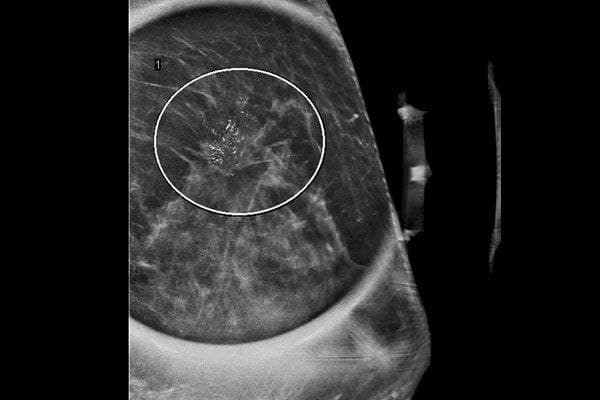

Unique Mass on High Risk MRI – 6 min